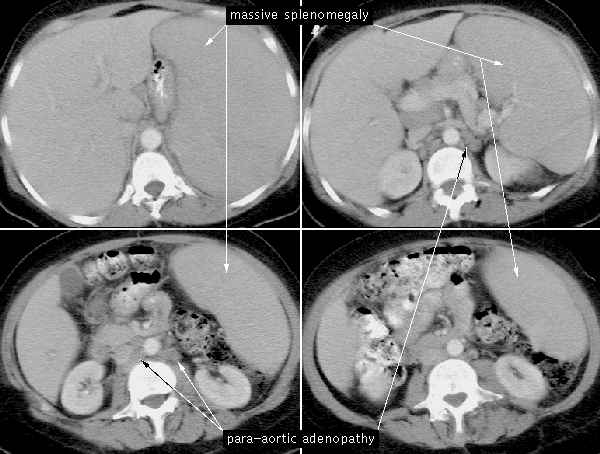

A twenty-six year old female presents to your Emergency Room after a motor vehicle accident. The patient reports that she was a pedestrian on South University Avenue and while crossing the street was struck by a car. The patient's only complaints are abdominal tenderness and left shoulder pain. On physical exam you note that her vital signs are: blood pressure (BP) 90/60, heart rate (HR) 110, and respiratory rate (RR) 12. Her abdomen is tender on palpation of the left upper quadrant, with a faint tire mark over that area; in addition you detect crepitus (indicating fractured ribs) over the 9th,10th, and 11th ribs on the left side. You order a CBC which demonstrates an increased white blood count and a decreased hematocrit. You perform a diagnostic peritoneal lavage (DPL) and order a CT . The DPL has a bloody drainage (through which you cannot read a newspaper) and CT confirms a complete splenic rupture and fractured ribs. The patient is taken to the O.R. for a splenectomy , and a pneumococcal vaccine is delivered to the patient.

Ribs 9, 10, and 11 lie over the region of the spleen; the spleen cannot normally be felt on deep palpation below the costal margin, unless significantly enlarged .

5. What are the signs and symptoms of acute splenic rupture?

Hypotension, left upper quadrant pain, peritoneal irritation, and referred pain to the left shoulder.